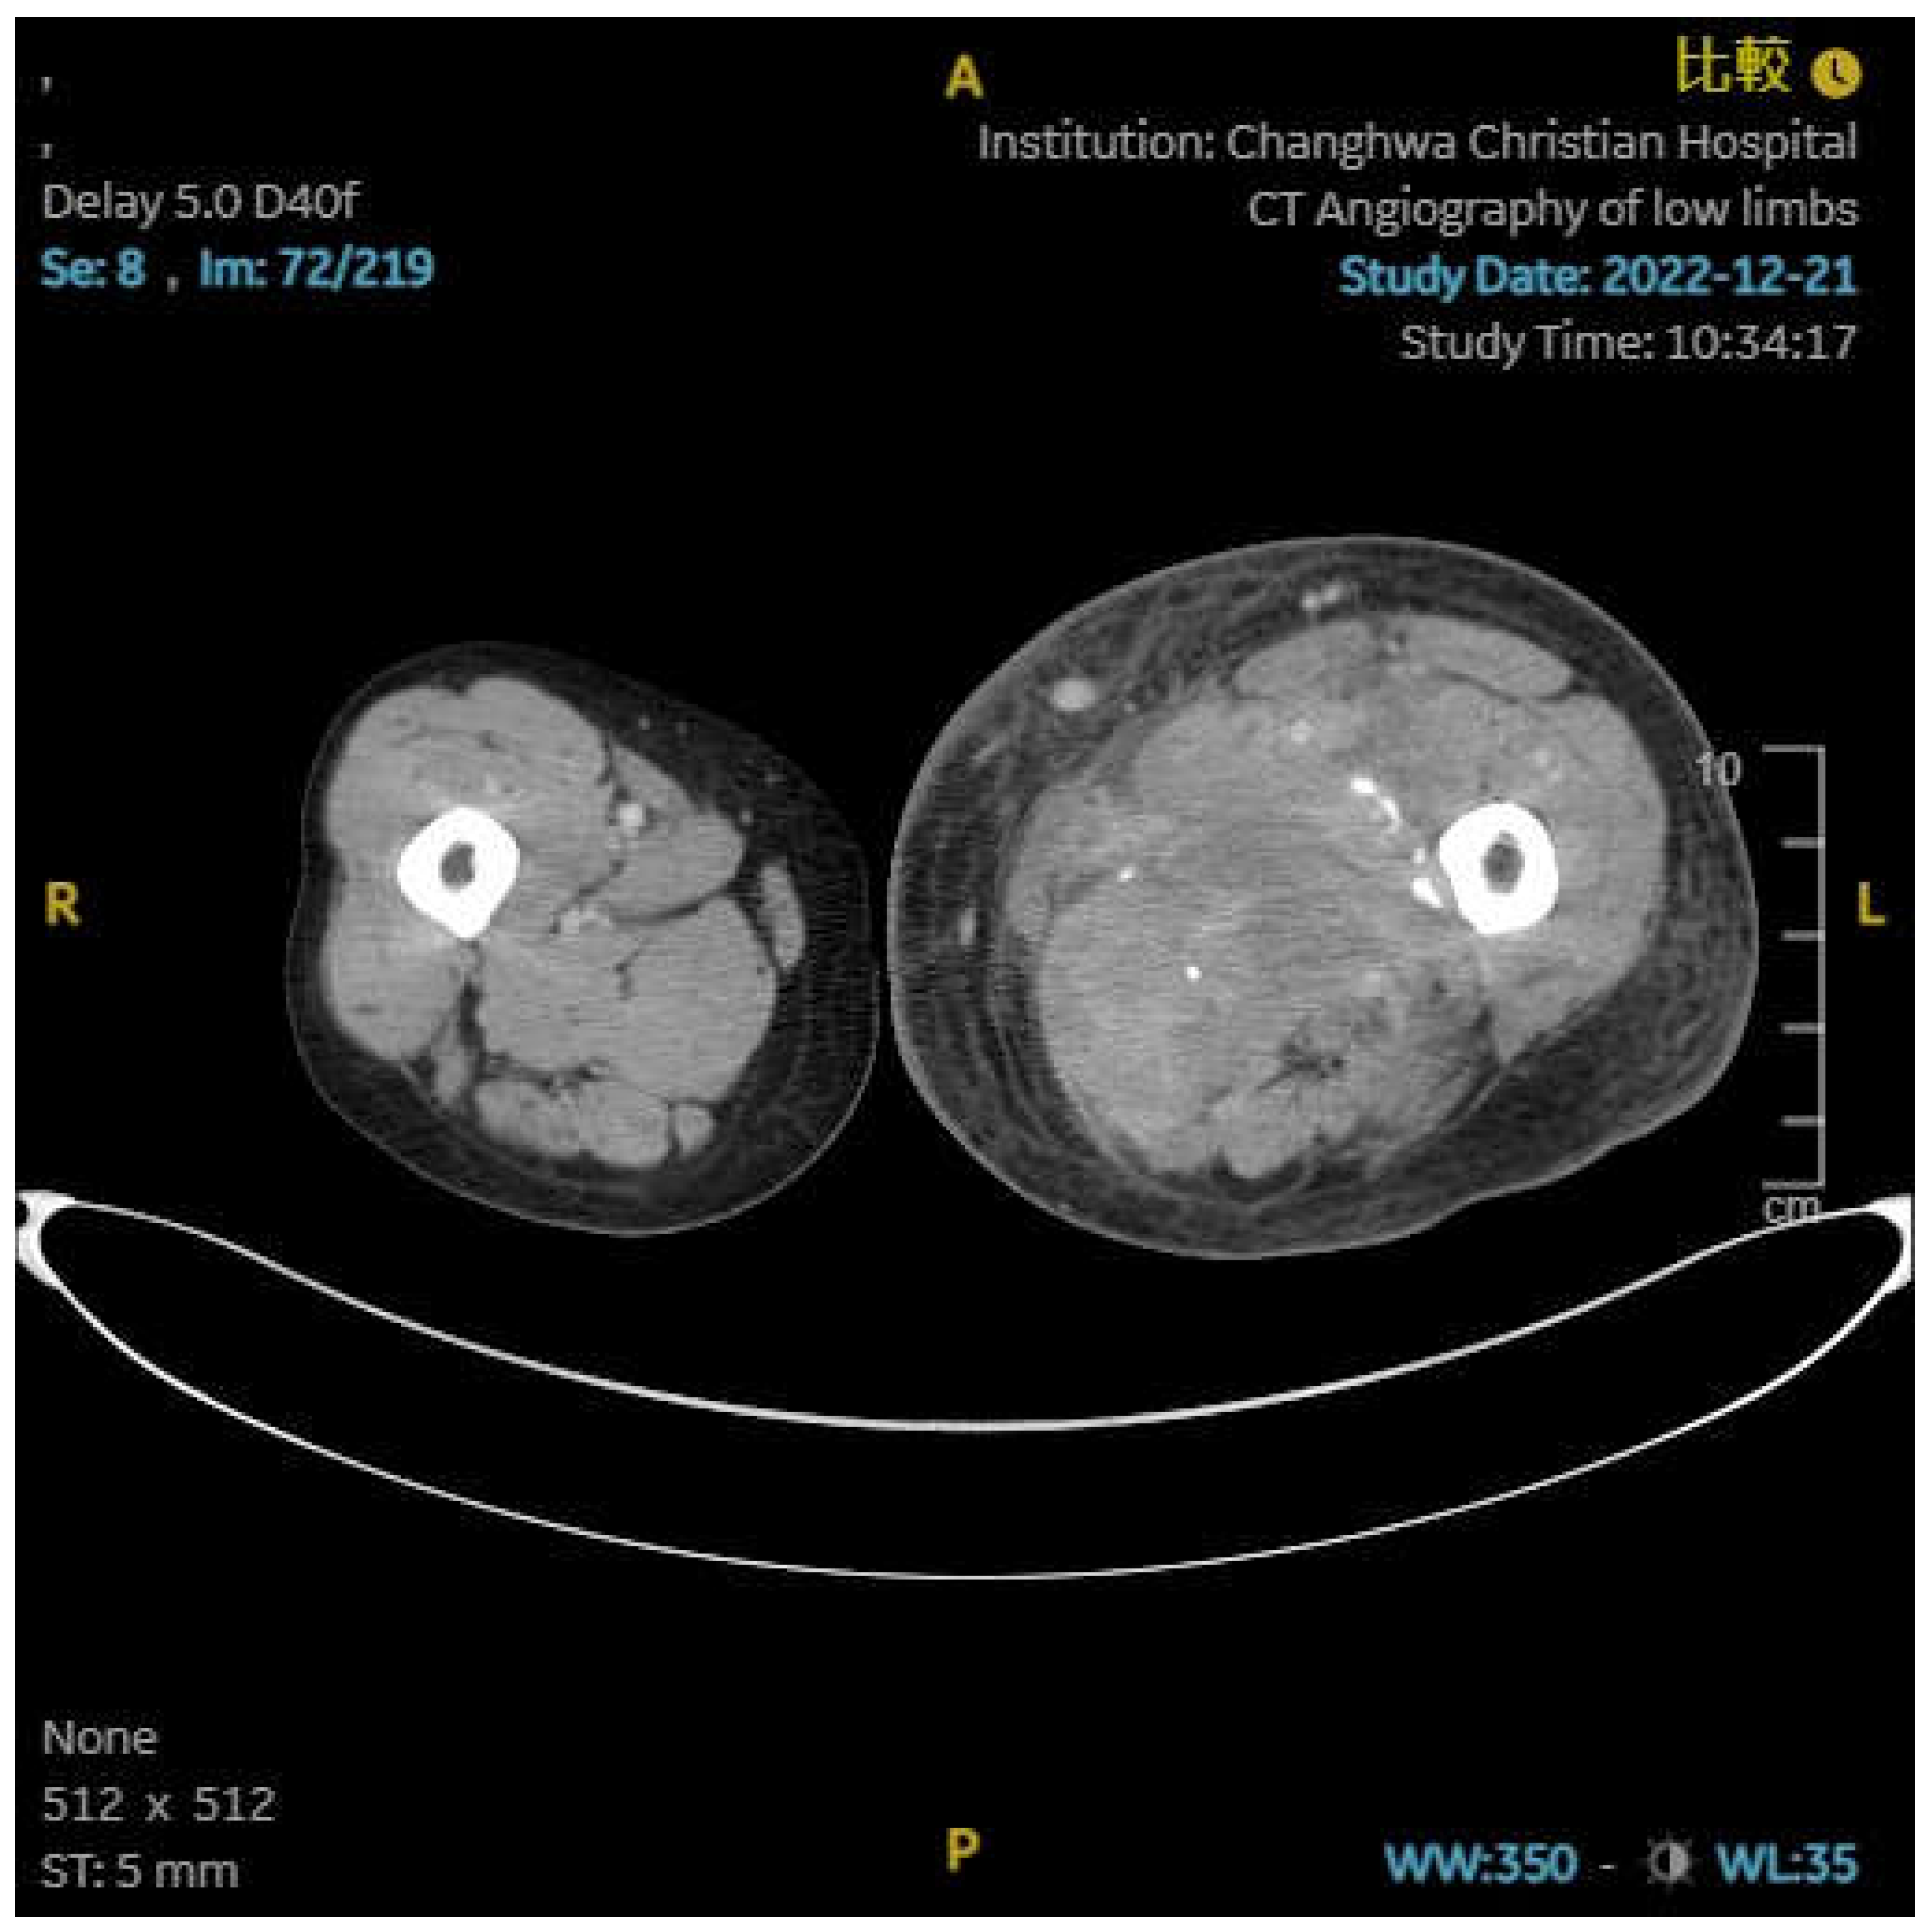

An 66-year-old female has a no medical history. She was presented with diarrhea, change in defecation habit and tenesmus and visited to outpatient department. On rectal examination, a annular mass was palpable at 5 cm from the anal verge. Biopsy from the mass showed adenocarcinoma. Pelvic magnetic resonance imaging and positron emission tomography were ordered and revealed rectal cancer, cT3N2M0. She was received neoadjuvant concurrent radiotherapy and chemotherapy followed by transanal total mesorectal excision with ileostomy. Pathology revealed pT3N2M0, stage III. She regularly visited outpatient department and ileostomy closure was applied after three months later. However, anal pain was complained. Anal nodule was found and biopsy revealed adenocarcinoma. Local recurrence was impressed and laparoscopic abdominoperineal resection was performed. We suggested infusion chemotherapy but she refused. Therefore, she was started on tablet capecitabine. After five months of operation, she complained left leg swelling. Abdominal computed tomography was ordered and it revealed May-Thurner syndrome with left side deep vein thrombosis. (Figure 1) Enoxaparin was prescribed first and rivaroxaban substituted it. Besides, stent was inserted. However, swelling persisted and lower limb computed tomography was ordered again 3 months later. It revealed May-Thurner syndrome post stenting, collapsed left proximal superficial femoral vein related to external compression, and diffuse calcification and area of low density in the left thigh muscle.(Figure 2,3) Computed tomography biopsy was applied and pathology revealed adenocarcinoma. On the other side, she had peritoneal carcinomatosis and intestinal obstruction and ileocecal bypass was performed. Target therapy with chemotherapy was given and she passed away one year later.

Figure 2,3. Abdominal computered tomography revealed diffuse calcification and area of low density in the left thigh muscle. (2) Coronal view (3) Transverse view.